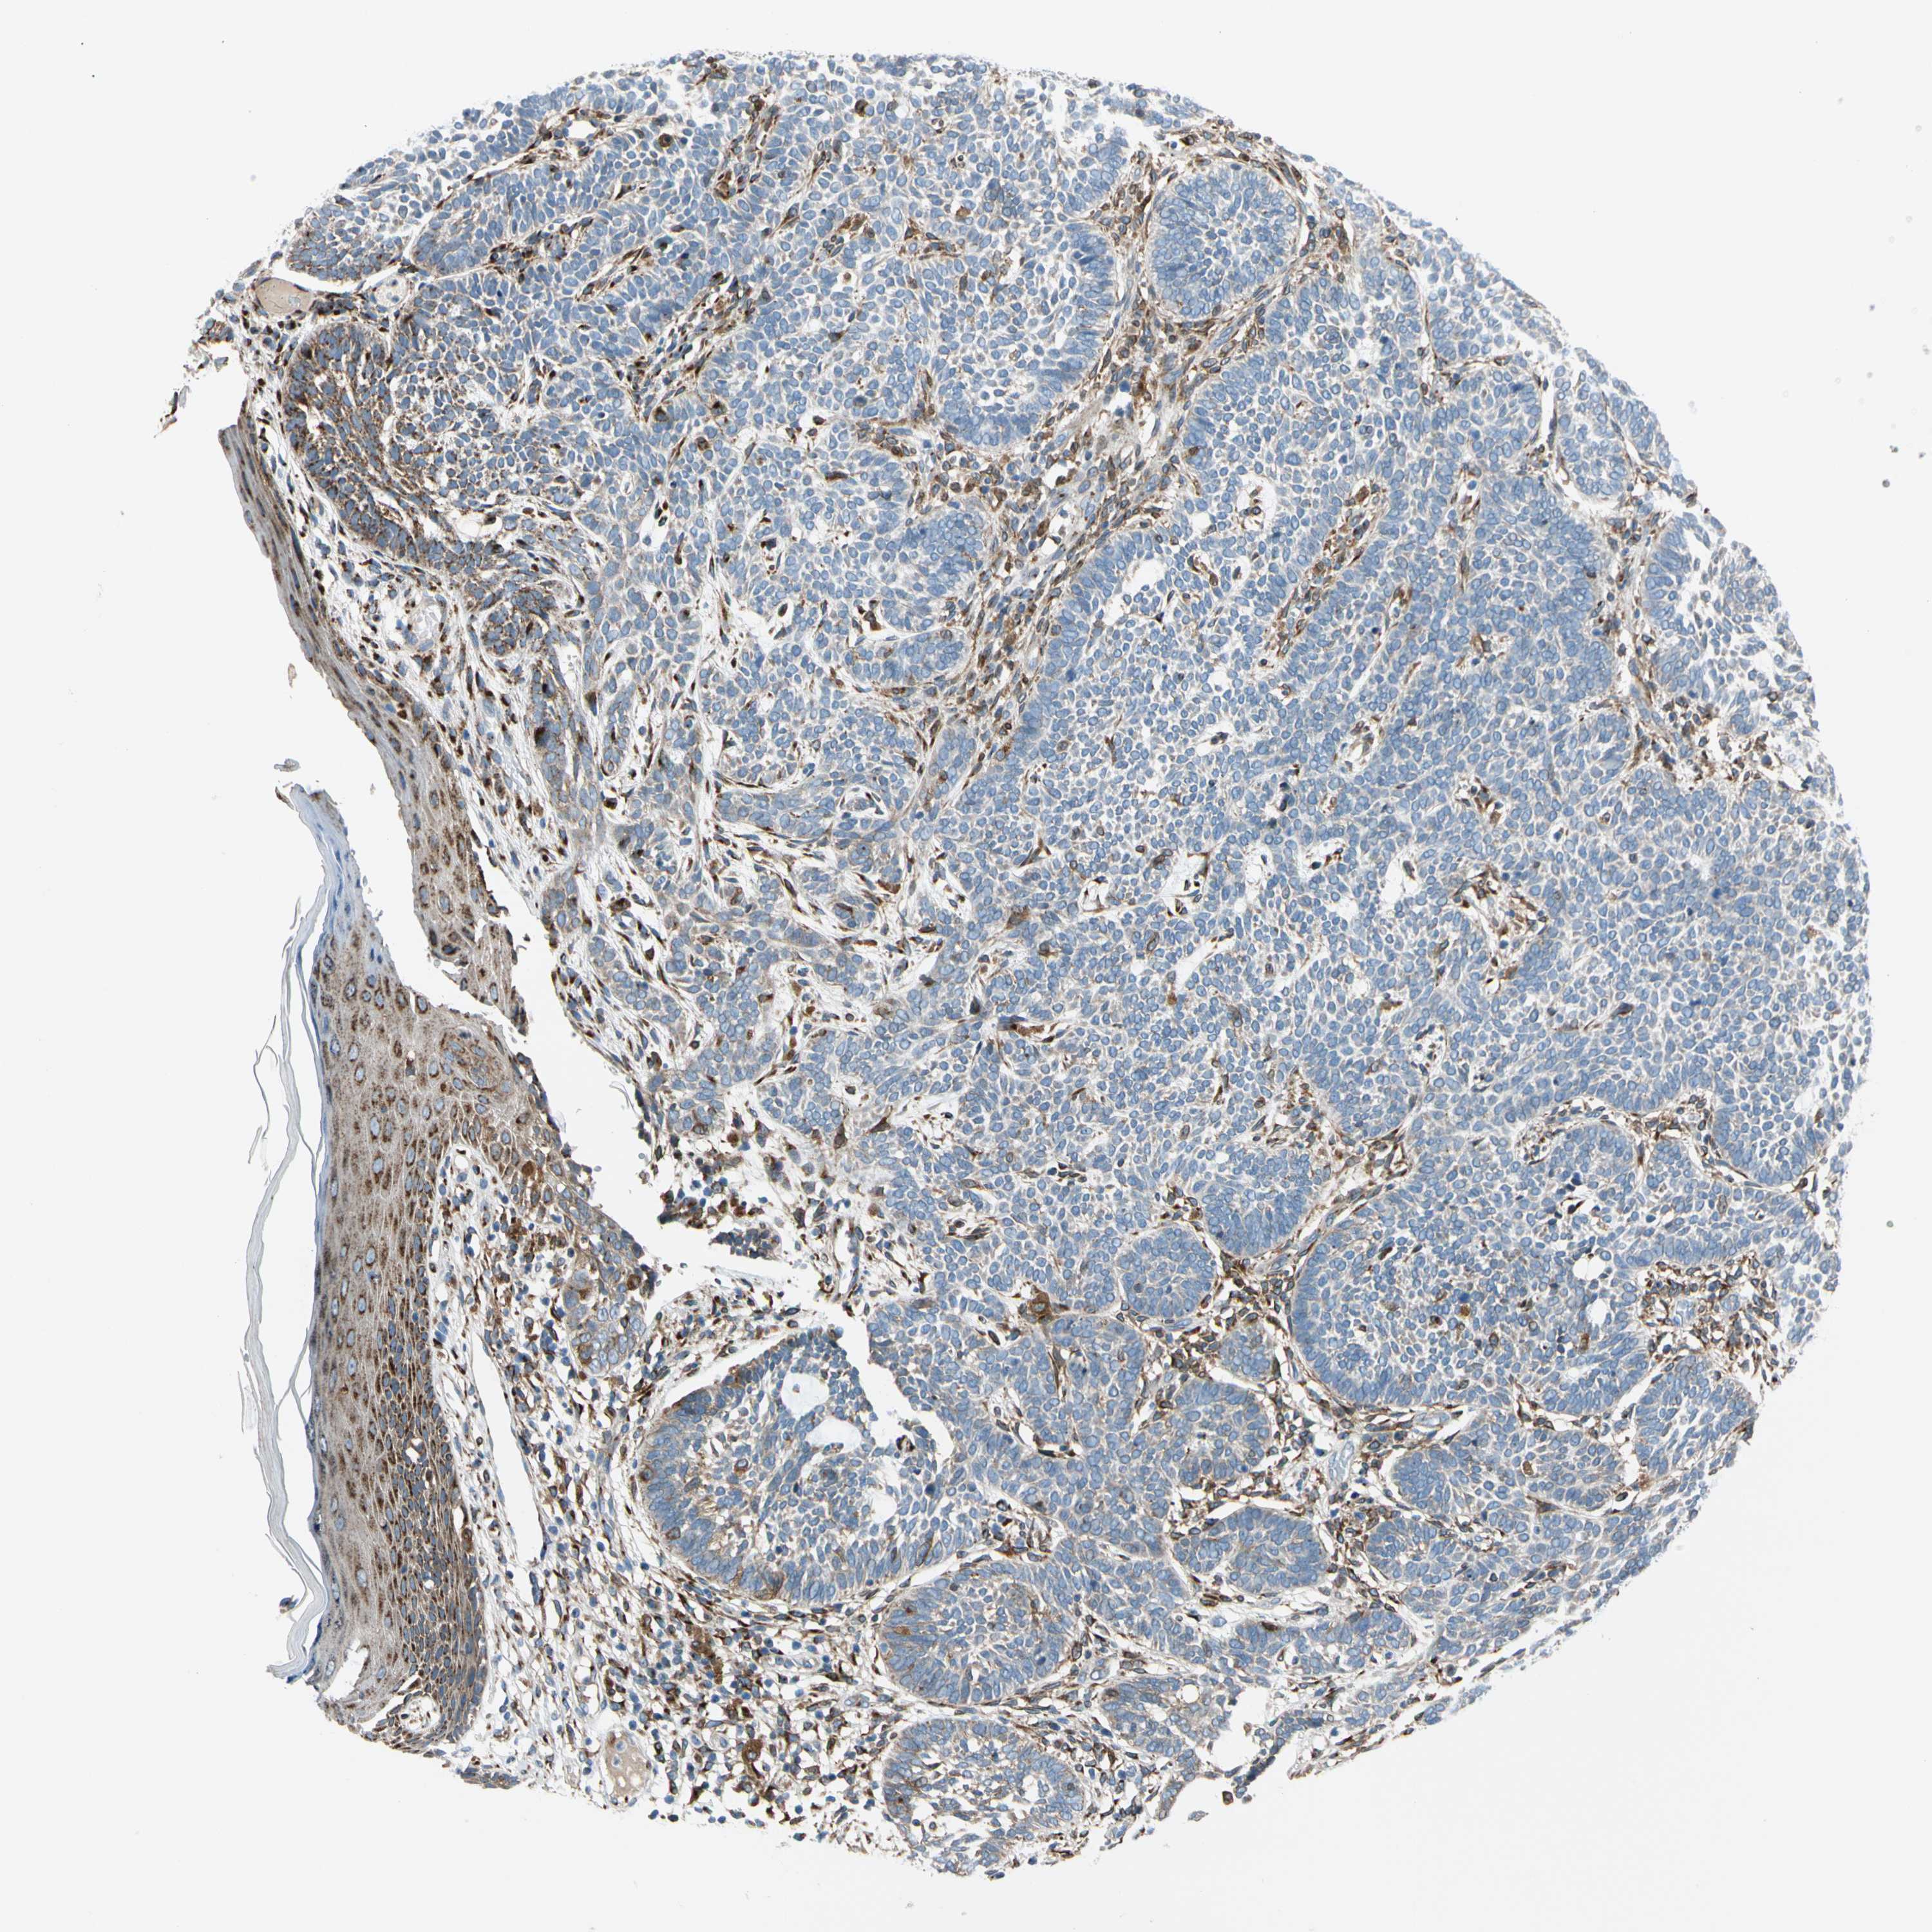

SKIN CANCER - Protein expressioni

A mouse-over function shows sample information and annotation data. Click on an image to view it in a full screen mode. Samples can be filtered based on level of antibody staining by selecting one or several of the following categories: high, medium, low and not detected. The assay and annotation is described here.

Each image is clickable and will lead to virtual microscopy that enables deeper exploration of all samples and also displays staining intensity scores, fraction scores and subcellular localization as well as patient and tissue information for each sample.

Antibody HPA008176

Staining

High

Intensity

Strong

Quantity

>75%

Location

Nuclear

Squamous cell carcinoma, NOS